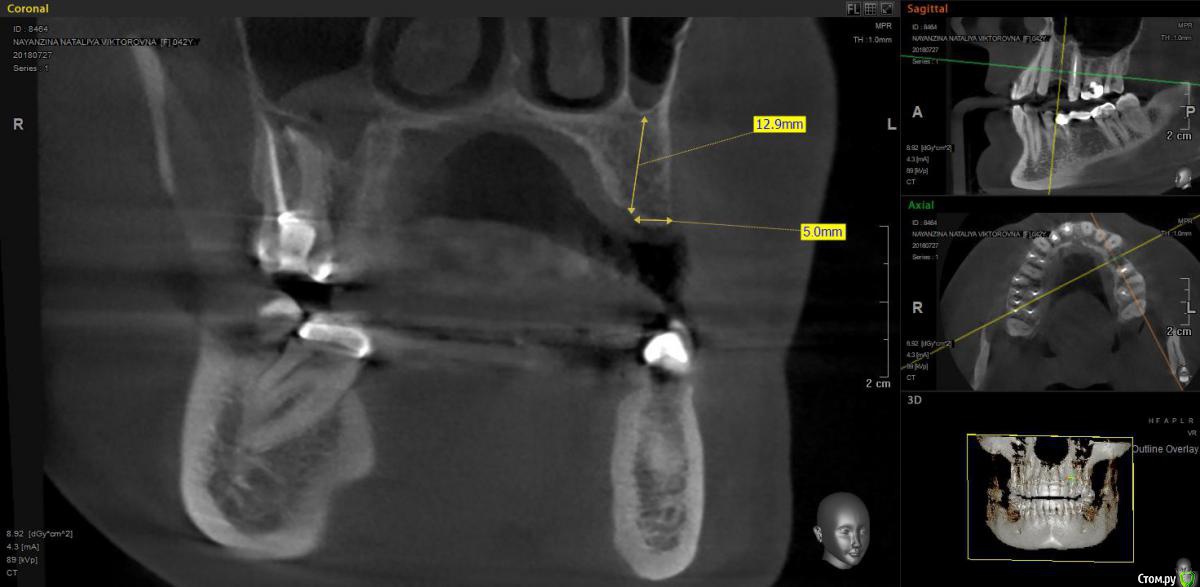

moises Опубликовано 8 августа, 2018 Поделиться Опубликовано 8 августа, 2018 Уважаемые коллеги,прошу совета.Необходимо установить имплантат коллеге.Обладаю базовыми навыками имплантации,то есть пока есть возможность брать только случаи с достаточным " костным предложением".Стоит браться в этом случае? (работаю альфа-био) Ссылка на комментарий

kramer Опубликовано 8 августа, 2018 Поделиться Опубликовано 8 августа, 2018 Я бы просто заглубил и поставил более небно, там дальше миллиметров 6 есть, 4х10 винт должен влезть 3 Ссылка на комментарий

moises Опубликовано 8 августа, 2018 Автор Поделиться Опубликовано 8 августа, 2018 Я бы просто заглубил и поставил более небно, там дальше миллиметров 6 есть, 4х10 винт должен влезтьВот так примерно? А вестибулярно косточку сглаживать или как есть этот козырек оставить? Ссылка на комментарий